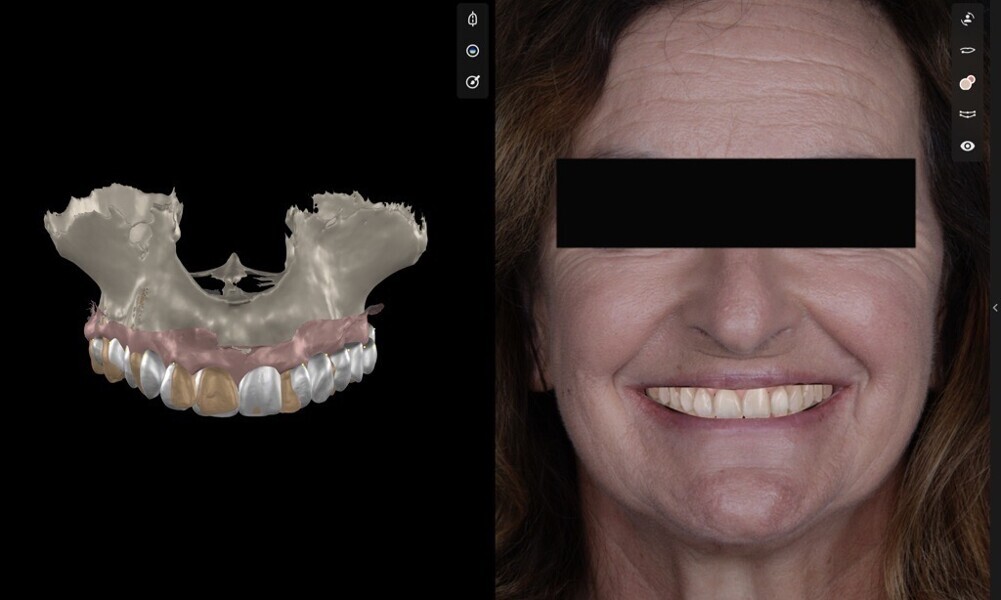

To ensure precise and predictable treatment planning, the DICOM files, STL files and clinical photographs were seamlessly integrated into Smilecloud, utilising advanced artificial intelligence technologies to deliver a highly personalised smile with exceptional precision (Figs. 11–15).

Figs. 11–15: DICOM files, STL files and clinical photographs were integrated into Smilecloud, leveraging artificial intelligence for precise, personalised smile design.